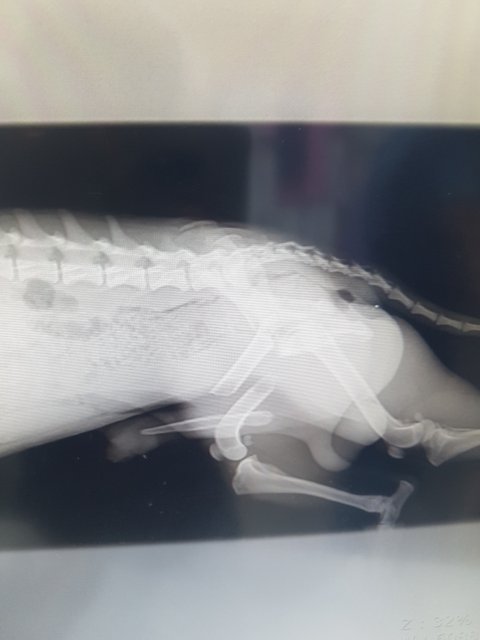

뒷다리골절과 사상충

뒷다리골절 덜렁거리는 다리로 꼬리를 흔들며 다가와 눈을 맞추던 아이..

눈속에 많은것을 담고 있던 아이를 능력이 안되지만 고통속에 둘수없어 병원으로 이동했습니다

대퇴부골절...

그리고 심한 사상충...

골절도 골절이지만 성충이 어마어마하게 많아 충을 꺼내는 수술을 해야할정도라고 합니다